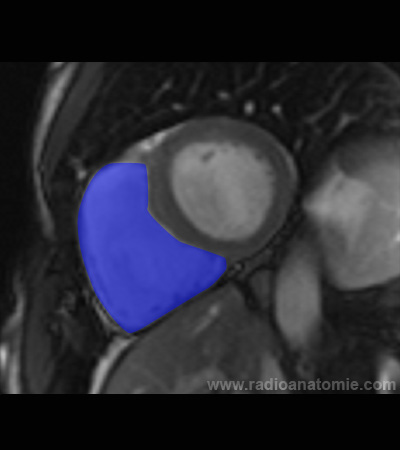

Radioanatomie et plans de coupe en IRM cardiaque

Ventricule gauche

Ventricule droit

Septum interventriculaire